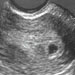

Bu gebelik haftasında ultrason yapıldığında yandaki görüntü elde edilir: Birkaç milimetrelik bir gebelik kesesi.

Gebelik kesesinde gelişmekte olan bebeğiniz henüz görüntülenecek kadar büyümemiştir.